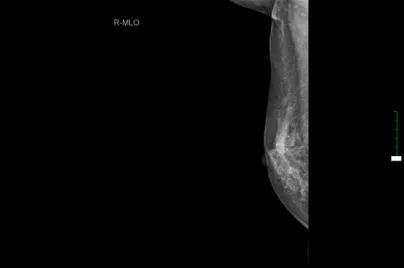

现病史:患者3年余前无意中发现右乳头后方有一肿块,约“枣样”大小,皮肤略红肿,无糜烂,乳头无溢血溢液,就诊于当地医院,建议定期复查处理。3年余来肿块逐渐增大,现约如“核桃样”大小,皮肤“橘皮样”变伴红肿,无发热,遂就诊于淮阳县人民医院,行乳腺彩超示:右乳实性占位(36x15mm),行乳腺钼钯示:右侧乳腺高密度块状影(2.9cmx4.0cm),建议进一步检查。今患者为求进一步诊治来我院就诊,门诊诊断为:“右乳肿块:乳腺癌?”,建议进一步治疗,遂收入院。

双乳彩超:右乳低回声肿块,BI-RADS 4C类,右侧腋窝淋巴结增大。